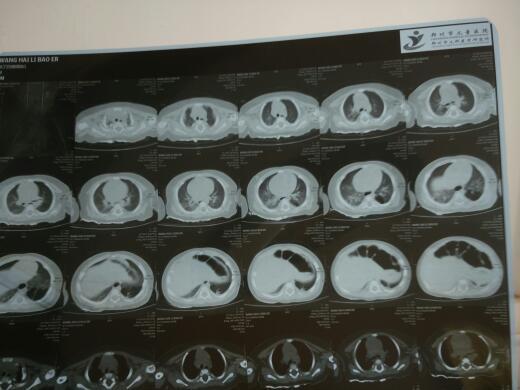

五个月大婴儿不发烧,每天大概咳嗽七八次,咳嗽时间长,憋的嘴唇发紫,在县医院治疗一周,诊断肺炎,后转诊省会医院呼吸科,诊断肺炎,做64排CT显示一侧肺部一段大概三分之一的区域有阴影,联合胸外科医师会诊,诊断肺囊肿,建议治疗好肺炎后,做肺部切除手术,下边是CT肺部图,请专家诊断诊断!